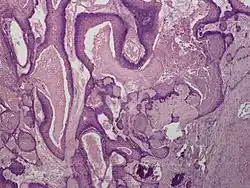

Proliferating trichilemmal cysts (also known as a pilar tumor, proliferating follicular cystic neoplasm, proliferating pilar tumor, and proliferating trichilemmal tumor)[1] is a cutaneous condition, characterized by proliferations of squamous cells forming scroll-like structures.[1][2]: 678

Histologically, Proliferating trichilemmal cysts are distinguished by trichilemmal keratinization, which is the sudden change from nucleated epithelium to anucleated keratinized cells without a granular layer.[4] The differential diagnosis include trichilemmal cyst and Turban tumor.[5]